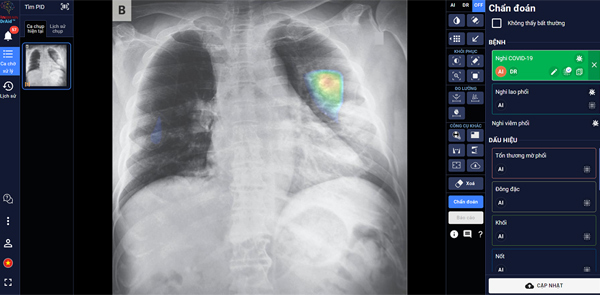

“DrAid for Radiology”- AI Trợ lý Bác sĩ cho Chẩn đoán hình ảnh y tế là sản phẩm đầu tay của VinBrain và cũng là sản phẩm ứng dụng AI hoàn chỉnh đầu tiên của y tế Việt Nam ra mắt phiên bản đầu tiên vào ngày 14/6/2020.

Theo đại diện VinBrain, sản phẩm có khả năng phát hiện, sàng lọc trên 21 dấu hiệu bất thường và bệnh lý về phổi - tim - xương trong vòng 5 giây với độ chính xác trên 89%; đồng thời có thể chia sẻ kết quả chẩn đoán thông qua QR code hoặc đường link. Đặc biệt, sản phẩm có khả năng tự cảnh báo Covid-19, kể cả các trường hợp không có triệu chứng hoặc tổn thương phổi nhẹ dựa trên X-quang ngực thẳng, kết hợp cùng xét nghiệm PCR giúp nâng cao độ chính xác, giảm thiểu tình trạng âm tính giả...

DrAid cũng nổi bật với tính năng “Hỏi ý kiến bác sĩ thứ 2 (từ xa)”. Thông qua việc chia sẻ hình ảnh trực tiếp từ DrAid, bác sĩ có thể hội chẩn từ xa với đồng nghiệp hoặc tham khảo ý kiến của các chuyên gia đầu ngành mà không bị ảnh hưởng bởi rào cản địa lý.

DrAid được Ban giám khảo ACM SIGAI đánh giá cao vì sản phẩm đã kết hợp và ứng dụng những kỹ thuật tiên tiến trong lĩnh vực trí tuệ nhân tạo như phân loại nhiều lớp, suy luận theo cấu trúc cục bộ đến tổng quan, học chủ động, đào tạo đối nghịch, mạng nơ ron tích chập phức hợp, nhận dạng giọng nói cho chỉnh sửa báo cáo Y tế tự động, khoanh vùng tổn thương trên ảnh Y tế với kiến thức máy học sử dụng công nghệ cao AI dựa trên mô hình với hàng trăm triệu tham số điểm ảnh (pixel) và dữ liệu lớn hàng triệu ảnh với mỗi ảnh có hàng triệu điểm ảnh (pixel), cùng nhiều kỹ thuật khác tạo nên một dịch vụ trí tuệ nhân tạo phục vụ Y tế toàn diện.